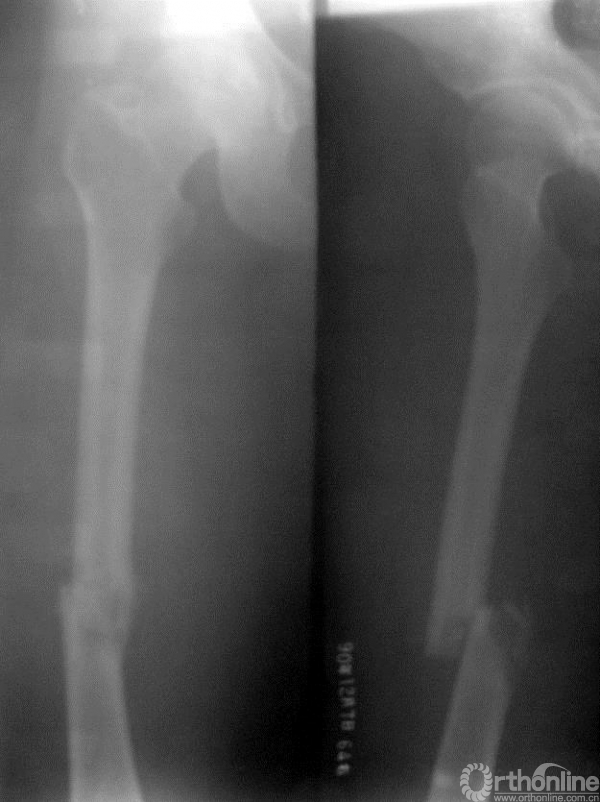

女性,33岁,入院2天前摔伤后出现右大腿肿胀、畸形、活动受限

图15-1 入院时X线平片正侧位,可见股骨中段病理骨折,骨折端可见溶骨性破坏

1.青年女性,X线显示股骨中段病理性骨折,折断可见溶骨性病变,边界较清晰。

2.一个月后的X线片显示皮质外形成骨痂,开始出现愈合征象

3.青年女性股骨中段的溶骨性病灶合并病理骨折,边界较清晰,且一个月后骨折出现愈合征象,考虑良性可能性大,例如骨囊肿,虽然儿童的骨囊肿多发生于长骨的干骺端,但在成人可移行于骨干,本病例不符合骨囊肿的是病灶位于股骨干中段,而不是偏干骺端的骨干,而且病灶边缘并不是很清楚,因此还应警惕恶性病变的可能。